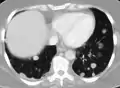

![]() | |

| Illustration showing hematogenous metastasis | |